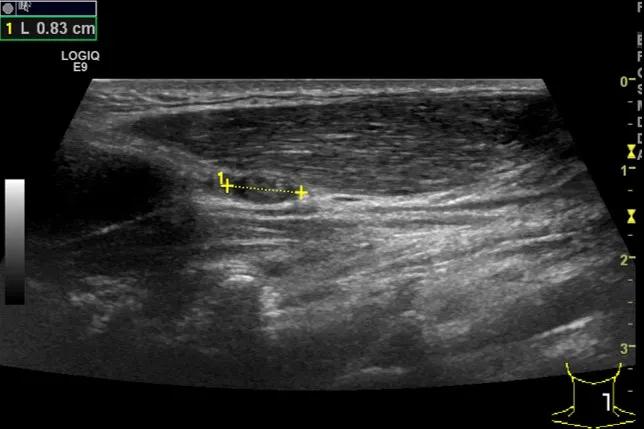

第二例是食管癌患者,术后半年余锁骨上固定淋巴结可触及肿大,疼痛非常明显,系统治疗后无缓解,患者希望通过局部处理缓解症状。造影显示强化信号明显,结节部分区域坏死,故主要针对强化区域从后向前的逐层的消融,皮下进行液体隔离减少烫伤。热消融后影像显示血流增强消失,弹性、硬度增高,一个月后复查显示充盈缺损,完全消融,疗效远超预期。

(病例2图例)